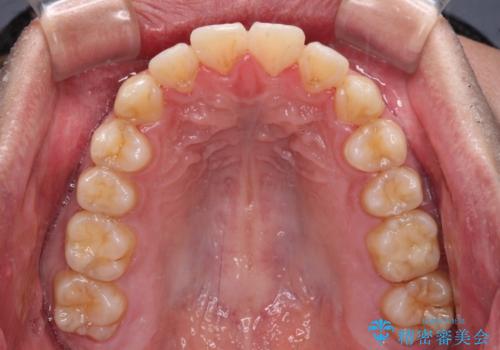

- 治療期間

- 9ヶ月

- 前歯のデコボコを治したいとのことで来院された患者様です。

できる限り楽して、短期間で治したいとのことで、ワイヤー装置にて矯正治療を行うこととしました。